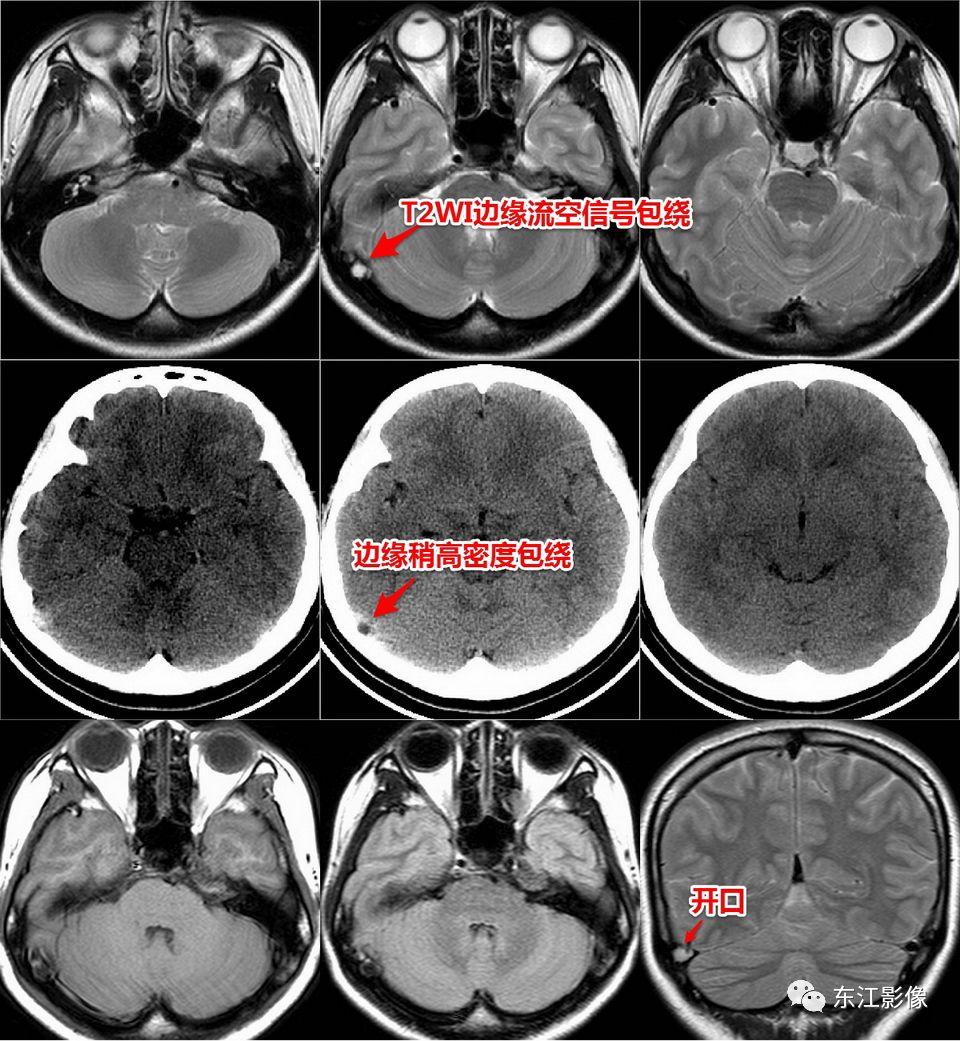

3. 颅骨蛛网膜颗粒压迹

- 是蛛网膜颗粒在颅骨内板及板障上形成的局限性压迹。

- 颅骨蛛网膜颗粒压迹广为人所熟知,但部分可能会被误诊为异常。

- 枕骨常见(横断面图像最容易被发现的缘故),额顶骨次之,颞骨少见。

- CT、MR表现为颅内凸入颅骨的充盈缺损,边缘锐利,无硬化;脑脊液样密度或信号,周围间隙清晰,无软组织肿块。

- 部分可穿颅骨内外板,容易被误认为异常。

双侧枕骨蛛网膜颗粒压迹。

双侧枕骨蛛网膜颗粒压迹,CT,MR比较。

顶骨蛛网膜颗粒压迹。